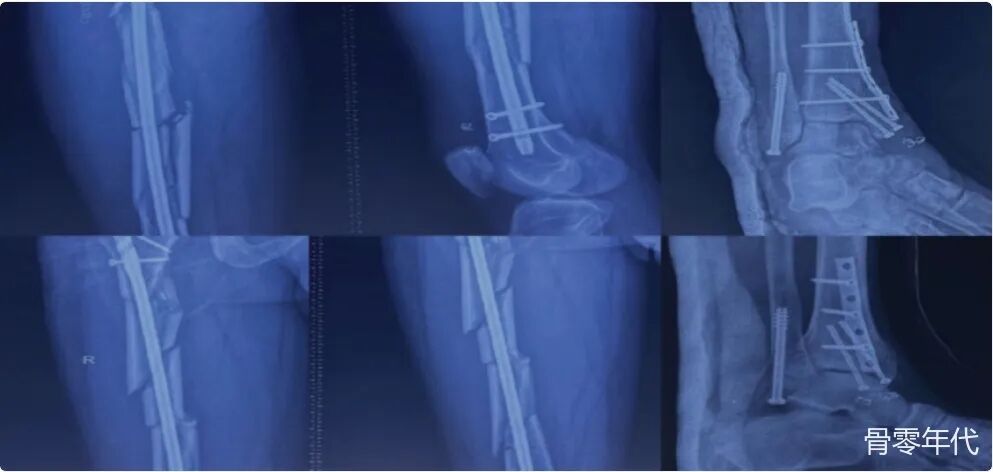

影像学表现